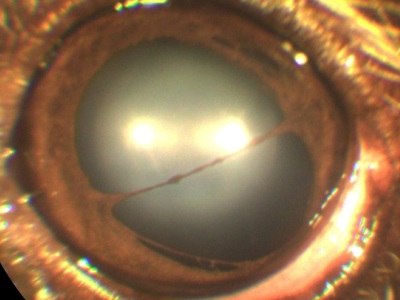

creșterea presiunii intraoculare (glaucom) va acționa, de asemenea, asupra celulelor endoteliale prin deteriorarea acestora.

coroida Inflamația (uveita) dă turbiditatea umidității în camera anterioară a vasului poate sângera de fibrina, lipide (în încălcarea metabolismului grăsimilor).

Infecțiile „Hyperimmunisation“ viermi intestinali, tulburări metabolice pot provoca inflamații (uveită).